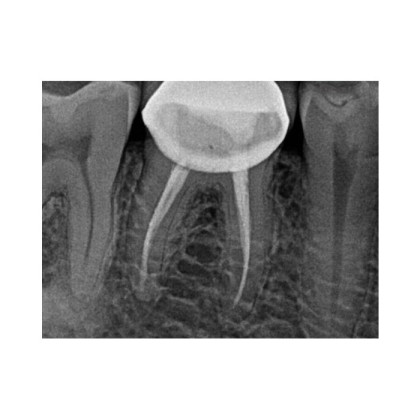

- Эндодонтия – контроль обработки корневых каналов.

⚙️ Передовые инструменты обработки изображений – улучшенная контрастность, фильтрация шумов, регулировка резкости для повышения качества диагностики.

| Разрешение пар линий | 16 |